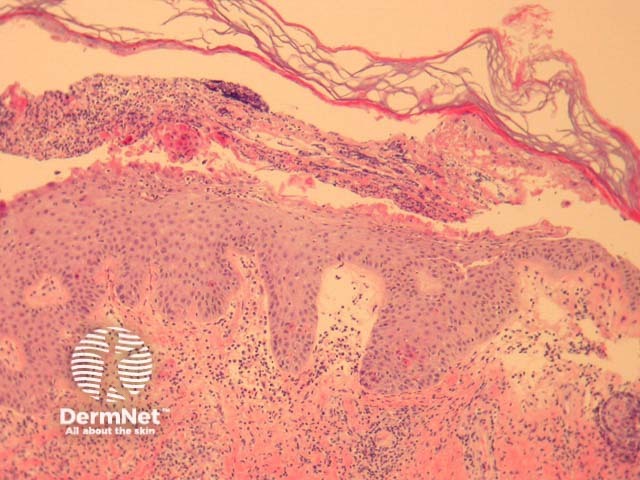

The bullous form of impetigo shows a subcorneal bulla with a dermal inflammatory response (figure 1). There are acantholytic cells in the superficial epidermis accompanying degenerated keratinocytes and small numbers of neutrophils (figure 2, 3). Gram positive cocci may be seen within the superficial epidermis.

The common type of impetigo shows subcorneal collections of neutrophils, serum and parakeratotic foci. There is usually a dermal inflammatory response. The organisms may be difficult to isolate with gram stains.

Figure 1

Figure 2

Figure 3